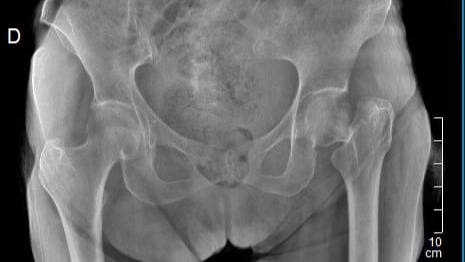

Hola, soy La Picua (Victoria) y a mis 83 años tuve una caida y me diagnosticaron fractura Transcervical del femur izquierdo y requiero de una operación e instalación de protesis para poder volver a caminar. Agradeceré enormemente su ayuda y colaboración.